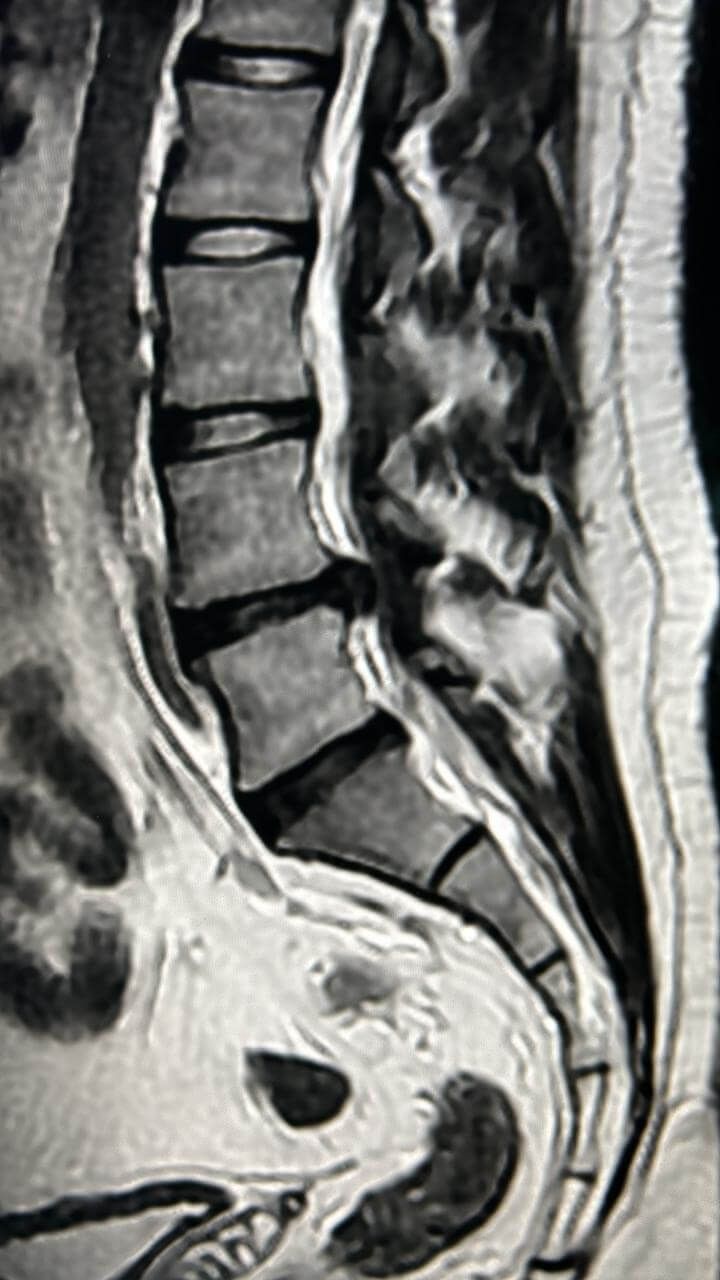

Cirugía de mínima invasión de columna vertebral

Realiza cirugías endoscópicas mínimamente invasivas de columna.

Ofrece diagnósticos y tratamientos especializados para la columna vertebral.

Cirugía de Columna

Realiza cirugía habitual y endoscópica mínimamente invasiva de columna vertebral.